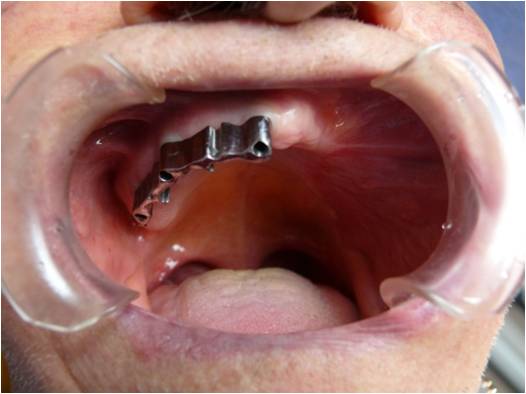

Chirurgia Oro-Mascellare per riabilitazioni protesiche post oncologiche

I pazienti che per motivi oncologici o per esito di osteonecrosi per uso di farmaci della categoria bifosfonati (in uso nelle gravi forme di osteoporosi o nel trattamento coadiuvante delle metastasi ossee)hanno subito gravi demolizioni dei mascellari e conseguente perdita della funzionalità masticatoria necessitano di ricostruzione e rifunzionalizzazione dell'apparato masticatorio con ricostruzione dell'osso mandibolare o del mascellare superiore attraverso innesti di osso , di lembi mucosi e/o muscolari di vicinanza ed a volte di implantologia preprotesica con impianti zigomatici , pterigoidei o convenzionali , tutto cio'con il fine di ripristinare una corretta funzione ma anche una auspicabile vita di relazione.

![]() | ![]() | ![]() | ![]() |